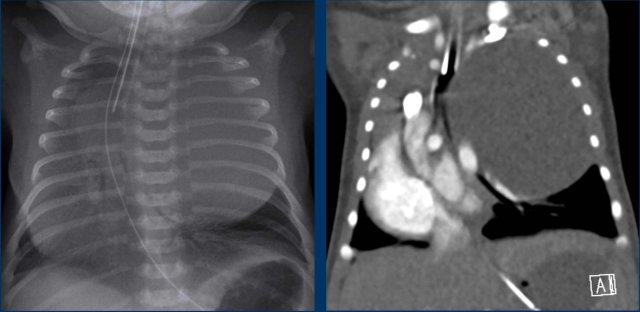

Images of   a neonate, 40 weeks gestational age.

Antenatal suspicion of large CPAM on the left side.

At birth respiratory distress

Images

Radiograph shows a large round opacified lesion.

Severe displacement of midline structures with atelectasis of the right lung.

Deep position ETT. NG tube in situ.

Because of the need of direct intervention a CT after IV contrast was performed.

CT shows a large cystic lesion in the upper lobe of the left lung, with displacement of vascular and bronchial structures.

The lesion has relation to any systemic vessel, Which excludes a sequester.

This is a CPAM, which is not yet aerated.